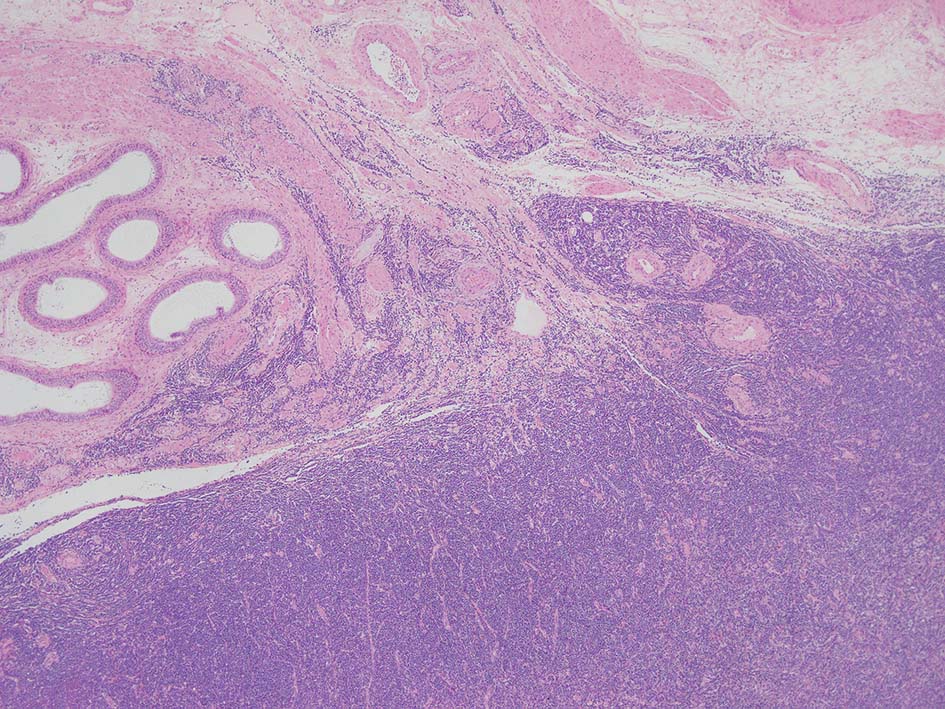

loupe像では, 腫瘍細胞が髄様密に浸潤増殖する部位と, 精細管をスペアするように管間に腫瘍細胞が浸潤する部分(右端図 A)がある.

切り出し図とは天地を逆にした右端図では, 髄様密な部分は白膜内で増殖するリンパ腫瘤(B)であることがわかる. 精巣上体の一部に浸潤がみられる(C)

loupe像Aの領域: 精細管をスペアするように, 小型リンパ球優位, 一部中型のlymphoid cellsがシート状密に浸潤増殖する. tubulesのほとんどにはlymphoid cellsが浸潤していないが, LELに似たようなlympho-tubular lesionが少数認められた. x400高倍率では, 増殖細胞は, 粗く, 凝集したクロマチンをもつ類円形, non-cleavedな核をもつ細胞質の乏しいlymphoid cellsである. 核小体か凝集したクロマチンかわかりにくい.

白膜には密に腫瘍性リンパ球が浸潤増殖し, 肥厚, 一部は上図loupe像のように, 腫瘤を形成している. 浸潤リンパ球は精巣実質内よりも, やや大きく, 多稜形, くびれのある核をもち, クロマチンは淡明で核小体が明瞭になってきている.